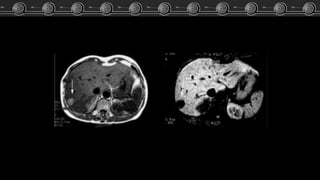

HiperplasiaNodular

Focal • Simple: Isodensa o

hipointensa.

• Fase arterial: hiperdensidad

transitoria, intensa,

homogénea.

TC

• Fase venosa: hipodensa o

isodensa.

• Tardías: isodensa, cicatriz

central hiperdensa.

• T1:

Isointensos o lig. hipointenso.

Cicatriz central: Hipointensa.

RM

• T2:

Hiperintensa a isointensa

Cicatriz central: Hiperintensa.

• T1 + C:

Hiperintensa homogénea.

Cicatriz hipointensa.